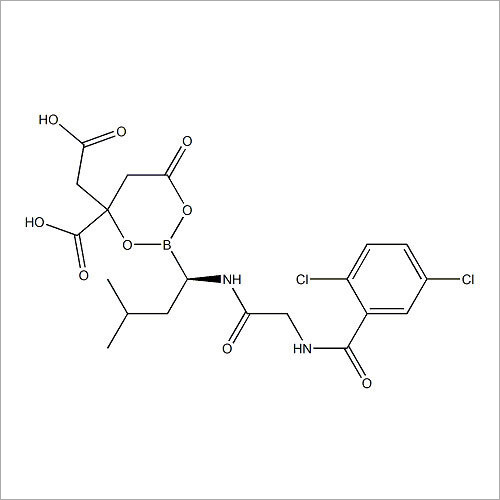

69558-55-0 थाइमोपेंटिन शुद्धता (%): > 99.0% (एचपीएलसी)

| रासायनिक नाम | Thymopentin |

| कैस नं | 69558-55-0 |

| रासायनिक नाम | Thymopentin |

| कैस नं | 69558-55-0 |